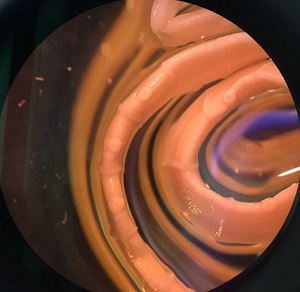

Figure A